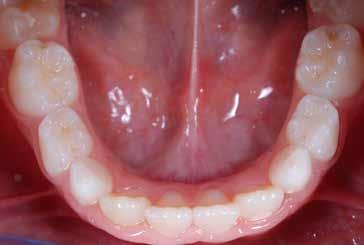

Fig. 126 > Immagine occlusale inferiore.

Fig. 19 > Dettaglio degli incisivi superiori.

57 > Immagine occlusale inferiore.